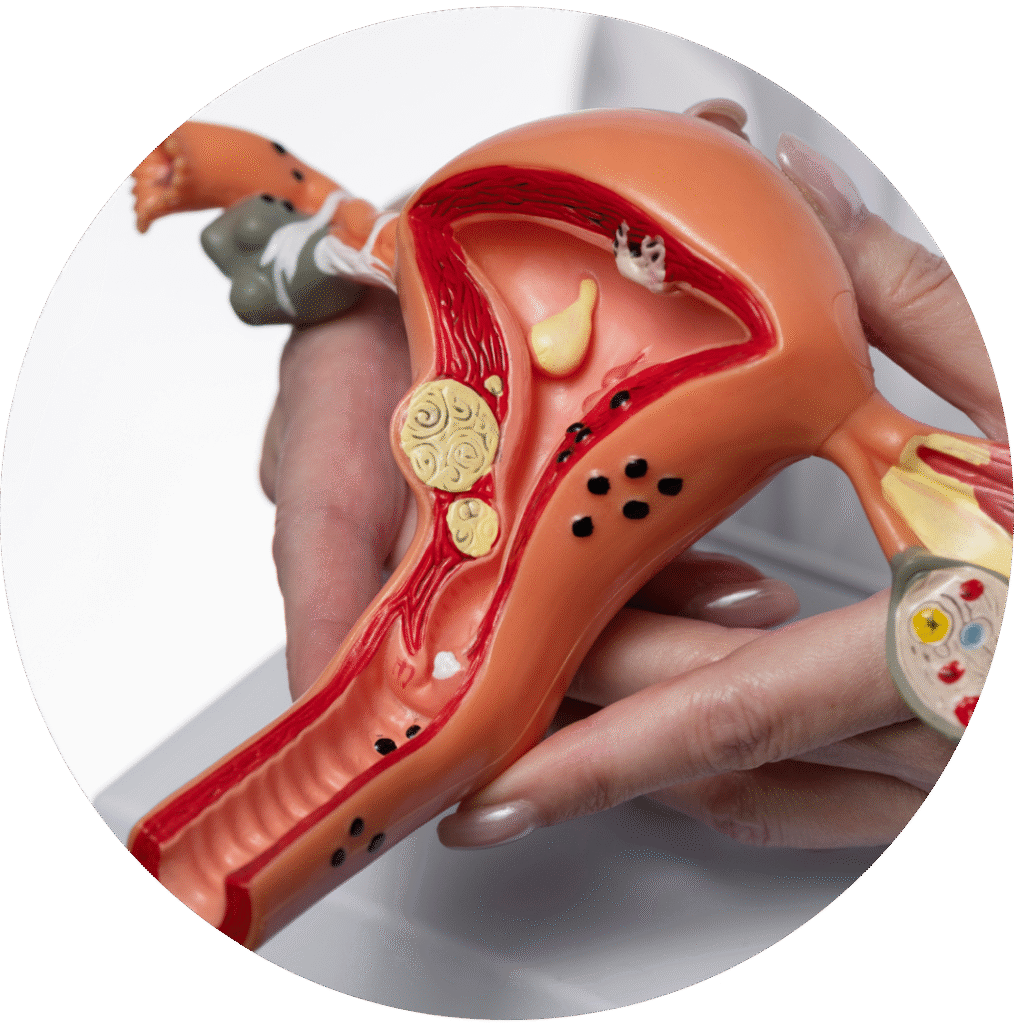

Abordagem cirúrgica especializada para câncer de ovário, útero, endométrio e outros tumores do sistema reprodutor feminino.

Cirurgias videolaparoscópicas para endometriose profunda, com abordagem multidisciplinar e foco em alívio dos sintomas.

Casos que envolvem múltiplos órgãos da pelve (útero, ovários, reto, bexiga), exigindo planejamento e atuação integrada.